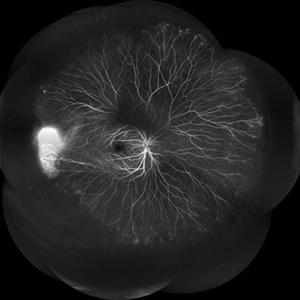

FEVR

Nov 22 2022 by Vaidehi Sathaye

Widefield FA montage of LE of a 23 year old male patient with FEVR

Photographer: Dr. Vaidehi Sathaye

Imaging device: Mirante

Condition/keywords: FA, familial exudative vitreoretinopathy (FEVR)